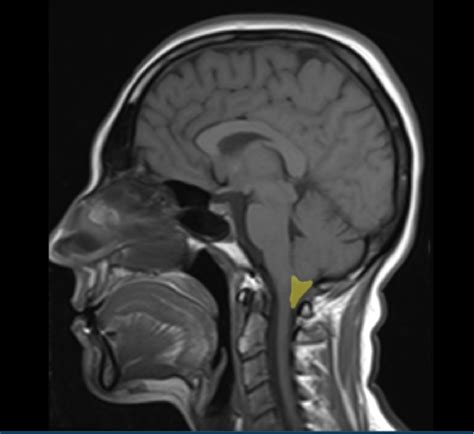

The Mega Cisterna Magna is a term used to describe an enlarged or dilated cisterna magna, a natural cavity in the brain filled with cerebrospinal fluid (CSF). The cisterna magna is a part of the subarachnoid space and is located at the base of the brain, between the cerebellum and the medulla oblongata. In normal conditions, it serves as a reservoir for CSF, which cushions the brain and spinal cord, providing mechanical protection and facilitating the exchange of nutrients and waste products.

The cisterna magna is situated in the posterior cranial fossa, a depression at the base of the skull. It is bounded by several important structures, including:

• The cerebellum, which is the part of the brain responsible for coordination and balance.

• The medulla oblongata, which controls vital functions such as breathing and heart rate.

• The tentorium cerebelli, a fold of dura mater that separates the cerebellum from the occipital lobes of the brain.

In the case of a Mega Cisterna Magna, this space is enlarged, which can be due to various reasons, including congenital anomalies, hydrocephalus, or other neurological conditions. The enlargement can be detected through imaging techniques such as magnetic resonance imaging (MRI) or computed tomography (CT) scans.